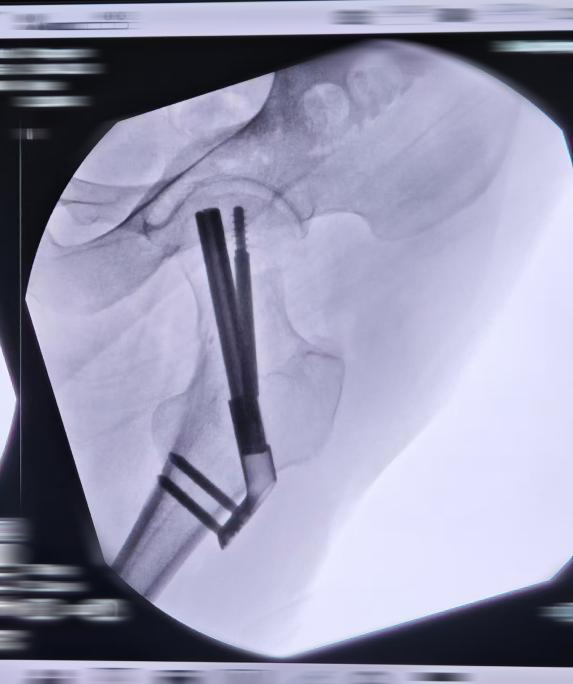

2.手术治疗:FNS股骨颈动力钉系统

FNS优势

更强抗旋效果:抗旋螺钉与固定钉相互锁定/且分叉(成角7.5°),有助于防止股骨头的旋转位移,相对于动力髋螺钉能够提供更好的防旋效果。

成角稳定:

板与固定钉之间成角稳定结构(130°颈干角),能够有效防止内翻塌陷和股骨颈短缩,相对于普通的中空螺钉治疗能够提供更充分的角稳定性。

术中主动加压/术后动力加压:固定钉和抗旋螺钉锁在一起,整体可动力加压,距离为20mm;外侧预留了足够空间,一定程度上避免外侧顶起引起的不适。

更小的植入物占位面积:

FNS对植入物尺寸进行了更小设计,允许小切口植入且外侧突出更少;植入物在骨面上的占位面积与三枚空心钉相似。